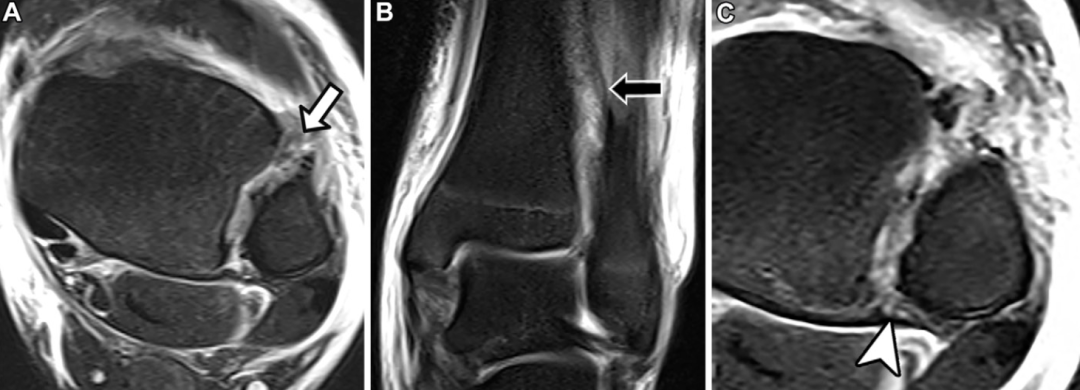

MRI检查

MRI是评估急性远端胫腓联合损伤的金标准影像学方法,据报道,其诊断前下胫腓韧带撕裂的准确率为76%~100%,诊断后下胫腓韧带撕裂的准确率为 88%~100%。MRI上,完整的胫腓联合韧带在所有脉冲序列中均表现为低信号的条带状结构。与其他韧带结构相同,根据影像学表现,胫腓联合韧带损伤可分为轻度扭伤、部分撕裂(中度扭伤)和完全撕裂(重度扭伤):扭伤表现为韧带增厚、信号增高及周围水肿;部分撕裂表现为韧带内局灶性连续性中断;完全撕裂则表现为韧带全层连续性中断或韧带缺如。

慢性损伤表现为韧带增厚、形态不规则,无明显周围水肿,此时诊断准确性显著下降,据文献报道,其敏感性为54%~62%,特异性为52%~61%。

不稳定性损伤的MRI诊断要点

尽管MRI能精准评估韧带和骨性损伤,但无法对远端胫腓联合进行动态评估。因此,MRI可显示解剖学损伤,但不能直接确诊关节不稳,仅能通过间接影像学表现推断。MRI上提示胫腓联合不稳的关键征象包括:后下胫腓韧带完全撕裂、后踝骨折、三角韧带完全撕裂及胫腓联合近侧腓骨骨折。

下胫腓后韧带完全断裂是判断胫腓联合不稳的可靠指标,其敏感性为74%,特异性为 78%,阳性预测值为54%。后踝骨折对关节生物力学的影响与下胫腓后韧带完全断裂相当,且单独发生的概率极低,仅占所有踝关节骨折的1%~4%:

但该骨折常合并更复杂的损伤,包括双踝骨折、三踝骨折和腓骨近端骨折。约82%的Maisonneuve骨折患者会出现后踝骨折的症状和体征。尽管单纯三角韧带损伤通常为稳定性损伤,但当其与远端胫腓联合损伤并存时,会导致踝关节冠状面明显不稳。